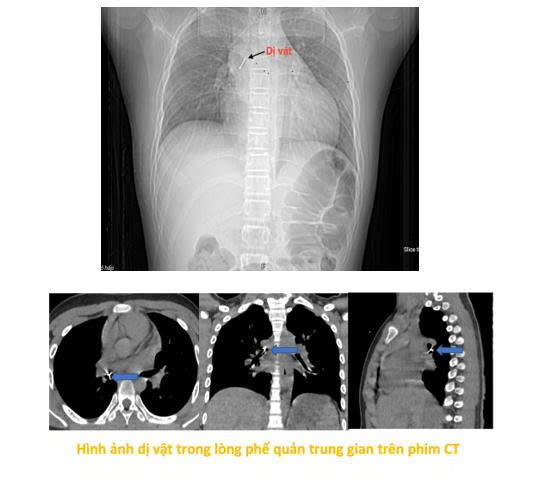

Theo gia đình bệnh nhi, vào tối ngày 13/10/2025, bé P.T.T.P (13 tuổi, Hà Nội) vừa ngồi xem điện thoại vừa ngậm chiếc đinh ghim bảng dài khoảng 2,5 cm. Trong lúc bé cười lớn, chiếc đinh bất ngờ rơi vào họng khiến bé ho sặc sụa, khó thở và cảm giác vướng ở ngực, nói khó. Gia đình hốt hoảng đưa trẻ tới bệnh viện gần nhà. Tại đây, bệnh nhi được làm các xét nghiệm máu, chụp phim cắt lớp vi tính lồng ngực, nội soi phế quản ống mềm, các bác sĩ xác định dị vật đã nằm sâu trong phế quản trung gian bên phải.

"Dị vật là chiếc đinh ghim sắc nhọn, nằm vướng tại phế quản trung gian, đầu nhọn đâm xuyên sâu vào thành phế quản. Đây là ca gắp dị vật rất khó, bởi ngoài tính chất, đặc điểm của dị vật như trên, bệnh nhi còn phản ứng theo phản xạ nên cần đòi hỏi thao tác nhanh, chính xác tuyệt đối để tránh làm rách thành phế quản hay đẩy dị vật xuống sâu hơn, có thể dẫn tới nhiễm trùng, chảy máu, tràn khí màng phổi, tràn khí trung thất. Thậm chí những biến chứng đó có thể gây hậu quả suy hô hấp cấp cho người bệnh. Do vậy sau khi đã đánh giá toàn diện kíp thực hiện đã cẩn trọng gỡ phần đầu đinh đang cắm vào thành phế quản thành trạng thái tự do bằng những dụng cụ kìm nội soi phế quản chuyên dụng, rồi từ từ gắp thành công dị vật ra ngoài. Quá trình diễn ra trong vòng 15 phút." bác sĩ Minh cho biết.